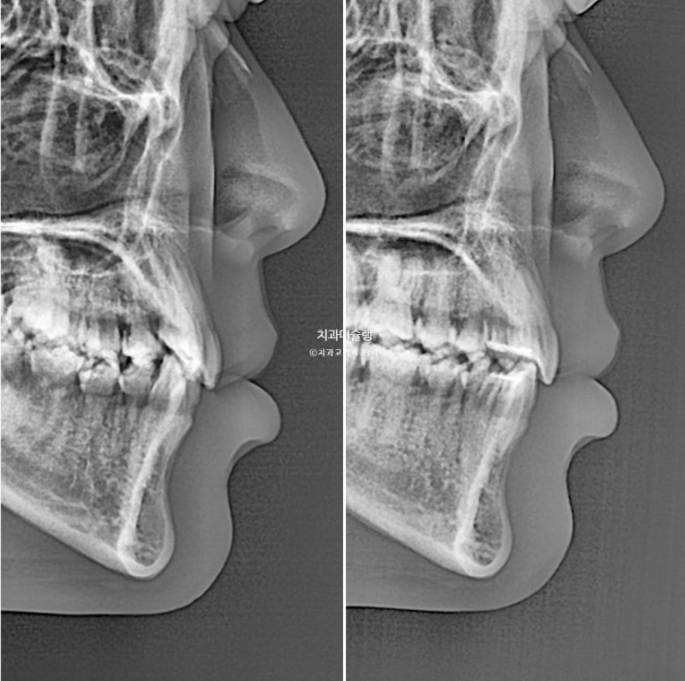

앞니는 뒤로 들어가지도, 나오지도 않고 잘 유지되었습니다.

23.08~25.10

전 후 입매 유지를 목표로 한 만큼 앞니 각도나 입매 변화는 없습니다.

발치교정은 하고 싶지 않은데 입이 나오거나 앞니가 뻗을까봐 걱정이신 분들에게